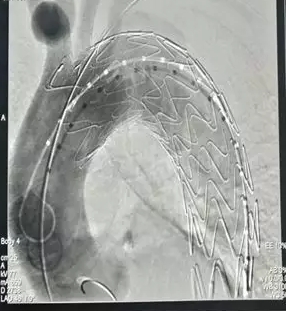

术中首先将体外开窗好的先健Ankura™ Pro主动脉主体覆膜支架输送到弓部,开窗位置对准颈总动脉后释放,然后从左肱动脉沿预置导丝送入裙边支架,精准定位后成功释放。最后,在左颈总动脉植入先健科技的Longuette™主动脉分支覆膜支架(裙边支架)保证开窗分支的血供。先健科技设计的裙边支架采用特殊的双层结构,其内层支架保证分支血管血液的通畅,外层裙边能有效封堵支架间的缝隙。术后造影显示,病变隔绝,分支血流通畅,裙边支架与主动脉支架贴合良好,术后效果良好。

(图:术后造影)